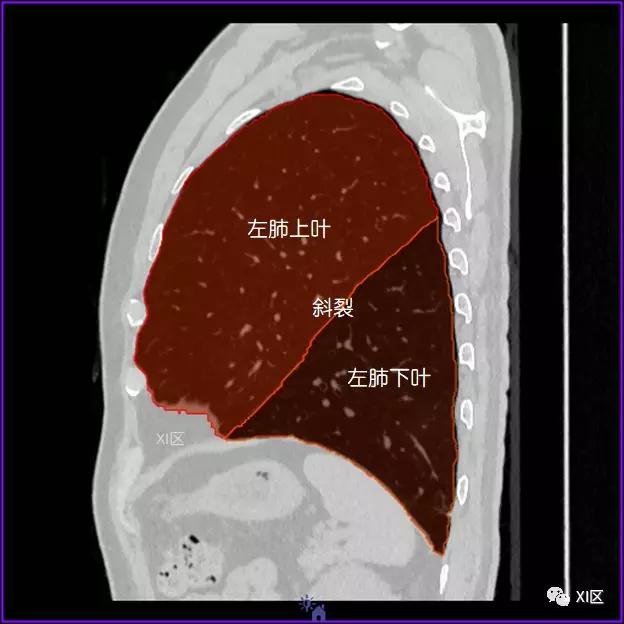

左肺借斜裂成上、下两叶;右肺借斜裂和水平裂成上、中和下叶三叶。

矢状位

肺表面重建显示叶间裂和肺的分叶

透视图显示肺的叶间裂和肺的分叶